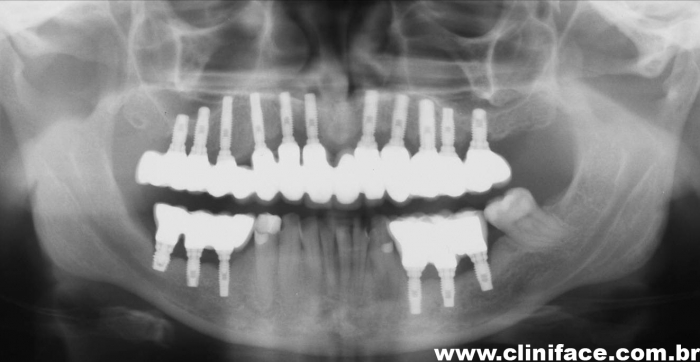

Raio X inicial